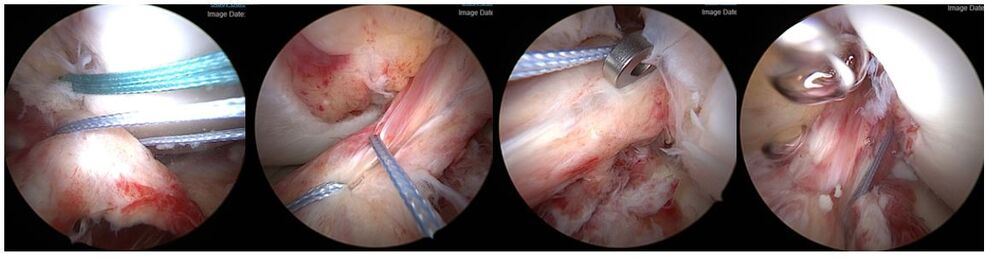

Eine Sonderform der Kreuzbandverletzung ist der knöcherne Ausriss des Bandes. Dabei kommt es bei der Verletzung nicht zu einer Ruptur des Bandes, sonders das Kreuzband reist mit einem Knochenstück ab. Meist ist dieser Ausriss dabei am Schienbeinkopf lokalisiert. Besonders gefährdet sind Kinder und Jugendliche, da bei diesen der Knochen meist weicher als die Bandstruktur ist. Die Symptome und Beschwerden entsprechen einer Kreuzbandruptur. Oft können die Verletzten das Bein nicht richtig strecken, da das Knochenstück einklemmt. Diese Verletzung ist im Gegensatz zu einer Kreuzbandruptur oft auch im normalen Röntgenbild des Kniegelenkes zu sehen. Zur Sicherung der Diagnose und um nach eventuellen Begleitverletzungen zu suchen, erfolgt oft ein MRT und manchmal auch eine Computertomographie (CT).